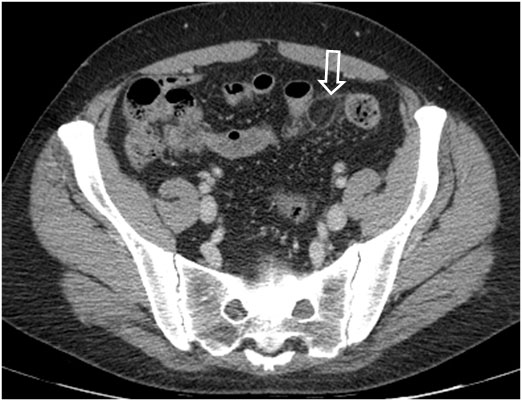

SIGNO DEL PSEUDOTUMOR

En la radiografía simple de abdomen, cuando un asa intestinal está obstruida por un vólvulo se llena de líquido y produce una falsa imagen de masa con densidad de partes blandas (flechas) que no debe confundirse con un tumor.

Este signo debe diferenciarse de las asas rellenas de líquido en la obstrucción mecánica simple. En la obstrucción en asa cerrada, la presencia del signo del pseudotumor indica que un asa intestinal se encuentra fija y permanece en la misma posición en todas las proyecciones.

En la imagen, pseudomasa causada por asas distendidas, con líquido, en la obstrucción intestinal.